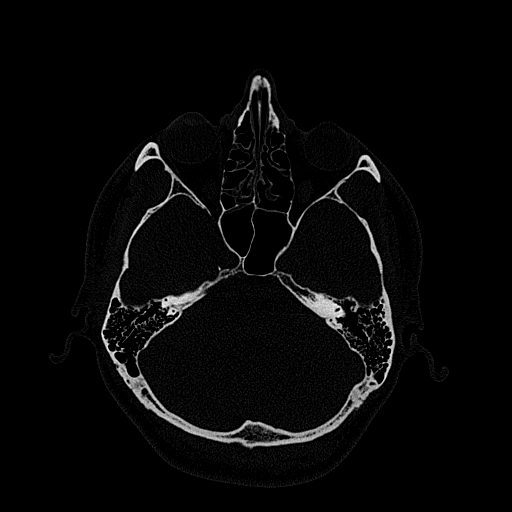

Мультиспиральная дентальная компьютерная томография (МДКТ или, как ее еще называют, КТ зубов) – это современный высокоточный метод лучевой диагностики, с помощью которого получают объемные цифровые изображения всей зубочелюстной системы. В основе метода лежит применение рентгеновского излучения и последующая цифровая обработка полученных данных специальными компьютерными программами.

Мультиспиральный томограф выполняет послойное сканирование области верхней и нижней челюстей с помощью рентгеновских лучей, а затем, используя компьютерную обработку данных, создает 3D-модели исследуемой зоны. Современные модели томографов проводят круговое сканирование по спирали, делая срезовые снимки на расстоянии 0,5 мм друг от друга. Затем на основе этих данных реконструируются детальные изображения челюстно-лицевой области в трехмерном формате.

- Широкие возможности диагностики. На трехмерных изображениях можно увидеть в целом верхнюю и нижнюю челюсть, включая гайморовы пазухи, височно-нижнечелюстные суставы. Помимо костной ткани при проведении КТ можно оценить состояние окружающих мягких тканей. Это бывает особенно важно при выборе оптимального способа протезирования и имплантации, при подозрении на опухолевые процессы, при планировании оперативного вмешательства.

- Толщину дна гайморовой пазухи, прорастание в нее зубного корня, распространение инфекционно-воспалительных процессов в пазуху со стороны зубов.